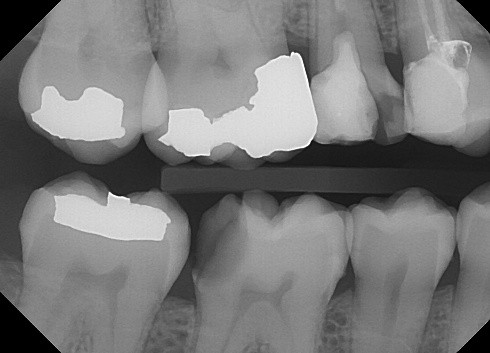

1. (Select ONE OR MORE correct answers)

The radiograph shows evidence of